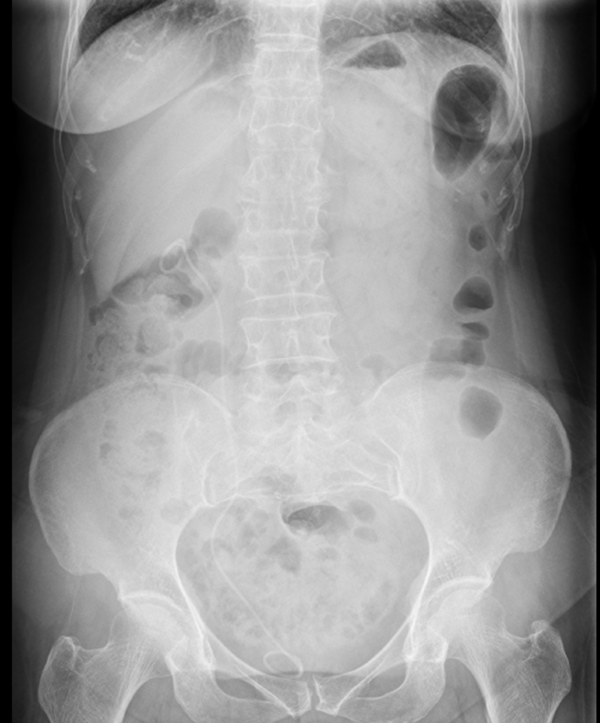

術(shù)后X線顯示結(jié)石被完全清理干凈